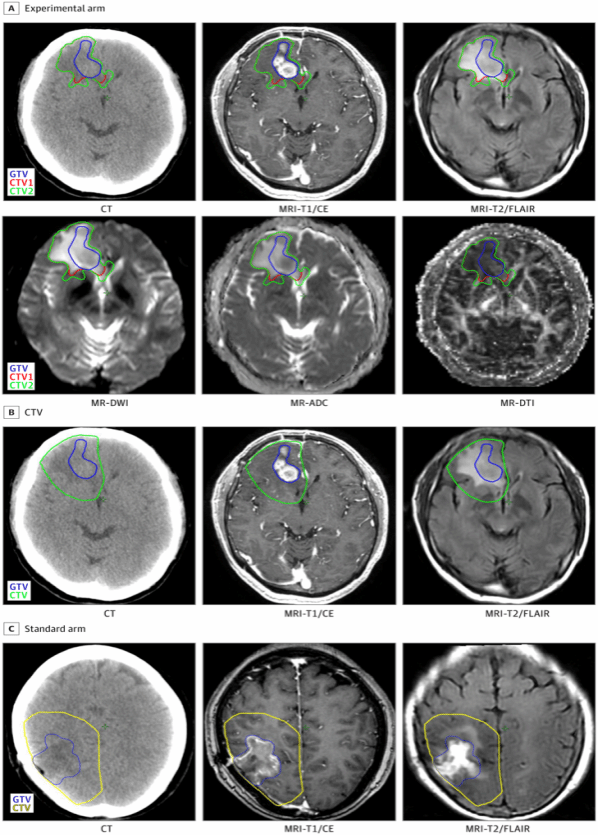

这项单中心、双臂、开放标签的随机临床研究招募了154名年龄在18至70岁之间、经组织学确诊为高级别胶质瘤(HGG)的初诊患者,试验组采用改良的靶区勾画联合HSIB-IMRT技术,研究结果显示,其临床疗效与标准调强放疗(IMRT)相当,但显著缩小了照射靶区体积,且未增加靶区外的复发率。

高级别脑胶质瘤(HGGs),尤其是胶质母细胞瘤带来了独特的神经认知负担:超过50%的脑或中枢神经系统肿瘤患者会出现中度至重度认知障碍,这是所有癌症类型中发生率最高的。Stupp方案即放疗联合同步及辅助替莫唑胺化疗,是当前新诊断胶质母细胞瘤的标准治疗方案,术后放疗照射靶区的推荐是在肿瘤、瘤床区结合解剖结构外扩1-2cm。如何提升肿瘤控制效果,又降低治疗相关毒性和治疗负担需要我们进一步优化治疗策略。该研究首次提出了一个关键问题:如何结合生物学特征与神经解剖学认知,运用新型影像技术为HGG患者制定合理的靶区方案。研究团队在采用HSIB-IMRT放疗技术同时通过整合三维磁共振波谱与神经纤维束解剖图谱等多模态MR影像,基于神经解剖学沿白质通路各向异性扩展照射靶区(覆盖细胞毒性水肿区外1厘米),避开信号正常的脑回及邻近风险器官。该策略使靶区体积显著减少60 cm³(22.5%)。

研究结果显示,在154例入组患者中(试验组76例,标准组78例),中位随访时间为22个月。试验组的无进展生存期(PFS)中位数为15.5个月,标准组为13.5个月(P = 0.89)。试验组的总生存期(OS)中位数为27.0个月,标准组为21.0个月(P = 0.24)。试验组的临床靶体积(CTV1:中位数116.7 cm;CTV2:中位数174.4cm)显著小于标准组(中位数225.0 cm³)(P < 0.001)。两组靶体积内、靶体积外及多中心复发率相当。试验组4例患者(5.3%)和标准组3例患者(3.8%)发生3级或4级不良事件(P = 0.72)。